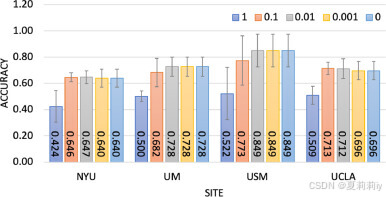

⑩Accuracy when adding different noise in Gauss mechanism (L2 norm and ):

the variable is